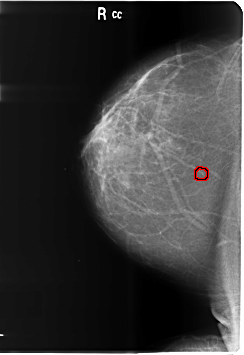

ics_version 1.0 filename B-3486-1 DATE_OF_STUDY 1 6 1998 PATIENT_AGE 39 FILM FILM_TYPE REGULAR DENSITY 1 DATE_DIGITIZED 4 6 1999 DIGITIZER LUMISYS LASER SEQUENCE LEFT_CC LINES 6016 PIXELS_PER_LINE 4128 BITS_PER_PIXEL 12 RESOLUTION 50 NON_OVERLAY LEFT_MLO LINES 6000 PIXELS_PER_LINE 4184 BITS_PER_PIXEL 12 RESOLUTION 50 NON_OVERLAY RIGHT_CC LINES 6024 PIXELS_PER_LINE 4144 BITS_PER_PIXEL 12 RESOLUTION 50 OVERLAY RIGHT_MLO LINES 6024 PIXELS_PER_LINE 4120 BITS_PER_PIXEL 12 RESOLUTION 50 OVERLAY |

FILE: B_3486_1.RIGHT_CC.OVERLAY TOTAL_ABNORMALITIES 1 ABNORMALITY 1 LESION_TYPE CALCIFICATION TYPE PLEOMORPHIC DISTRIBUTION CLUSTERED ASSESSMENT 4 SUBTLETY 3 PATHOLOGY BENIGN TOTAL_OUTLINES 1 BOUNDARY |